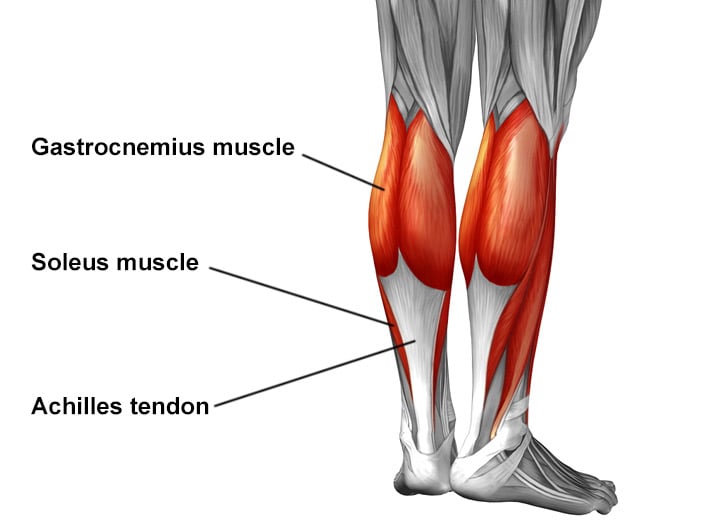

Achilles tendon anatomy

The Achilles tendon is a thick tendon located in the back of the lower leg. It connects the gastrocnemius and soleus muscles in the calf to an insertion point at the calcaneus (heel bone). It is the strongest tendon in the body and allows people to push off while walking, running, and jumping.